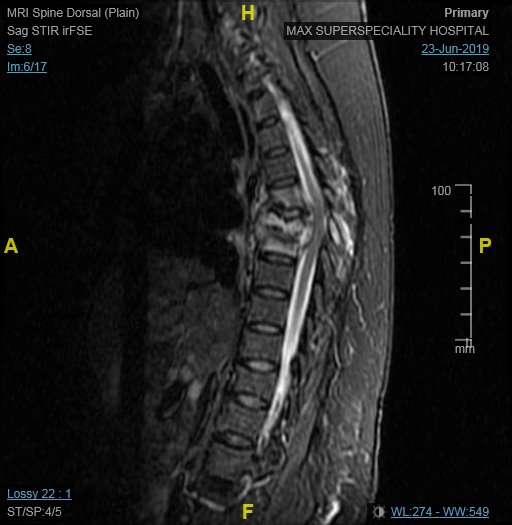

Spinal Tuberculosis

Tuberculosis of spine is the commonest form of the disease after the one involving the lungs. Pain over the spine and back is the initial symptom, followed by weakness of the limbs due to compression of the spinal cord due to formation of pus and collapse of spine. Complete evaluation by MRI, followed by surgery at appropriate level results in rapid recovery and early return ot work. Surgery may have to be accompanied by insertion of spinal implants to achieve stability and pain free back. Complete course of antituberculous drugs is mandatory for cure.